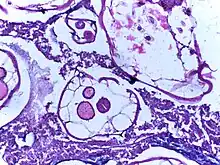

Micrograph of cut section of human appendix showing a pin worm.